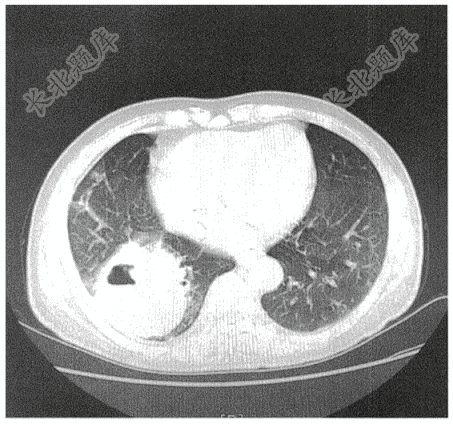

- 简答题患者女性,75岁,咳嗽、咳痰3个月,加重伴咯血2周,胸部CT如下: